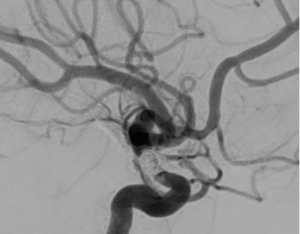

Coiling with assisted technologies

Coiling has evolved to incorporate numerous technologies aimed at enhancing the durability of treatment and preventing recurrence over time. Some of these advancements include the use of stenting or balloons to secure the coils within the aneurysm, as well as the utilization of temporary stents. Our research in this area has focused on evaluating factors predicting recurrence after treatment, comparing various technologies and outcomes in the short and long term. Additionally, we have validated scoring systems predicting recanalization at a multi-institutional level.